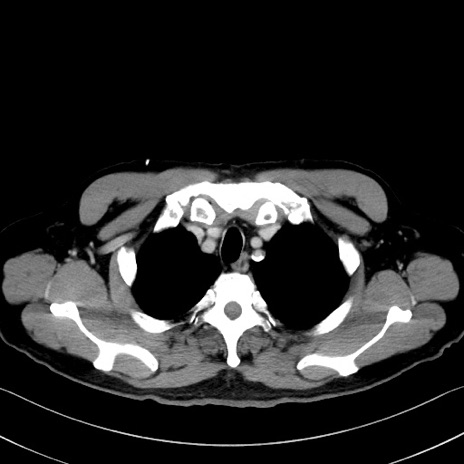

症例35(横断像)

【症例】70歳代 男性

【主訴】腹部膨満、嘔吐

【現病歴】昨日より腹部膨満感出現。本日増悪し、仙痛出現。嘔吐あり、受診。

【既往歴】糖尿病、胆摘後

【身体所見】BP 149/80mmHg、HR 74/min、BT 35.9℃、腹部:膨満、軟、圧痛なし。腸雑音減弱あり。上腹部正中切開瘢痕あり。

【データ】WBC 13500、CRP 1.72